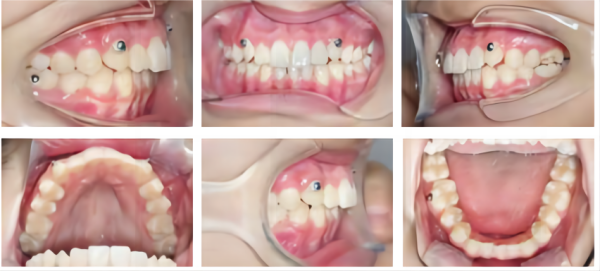

During Treatment

Intra-oral photos